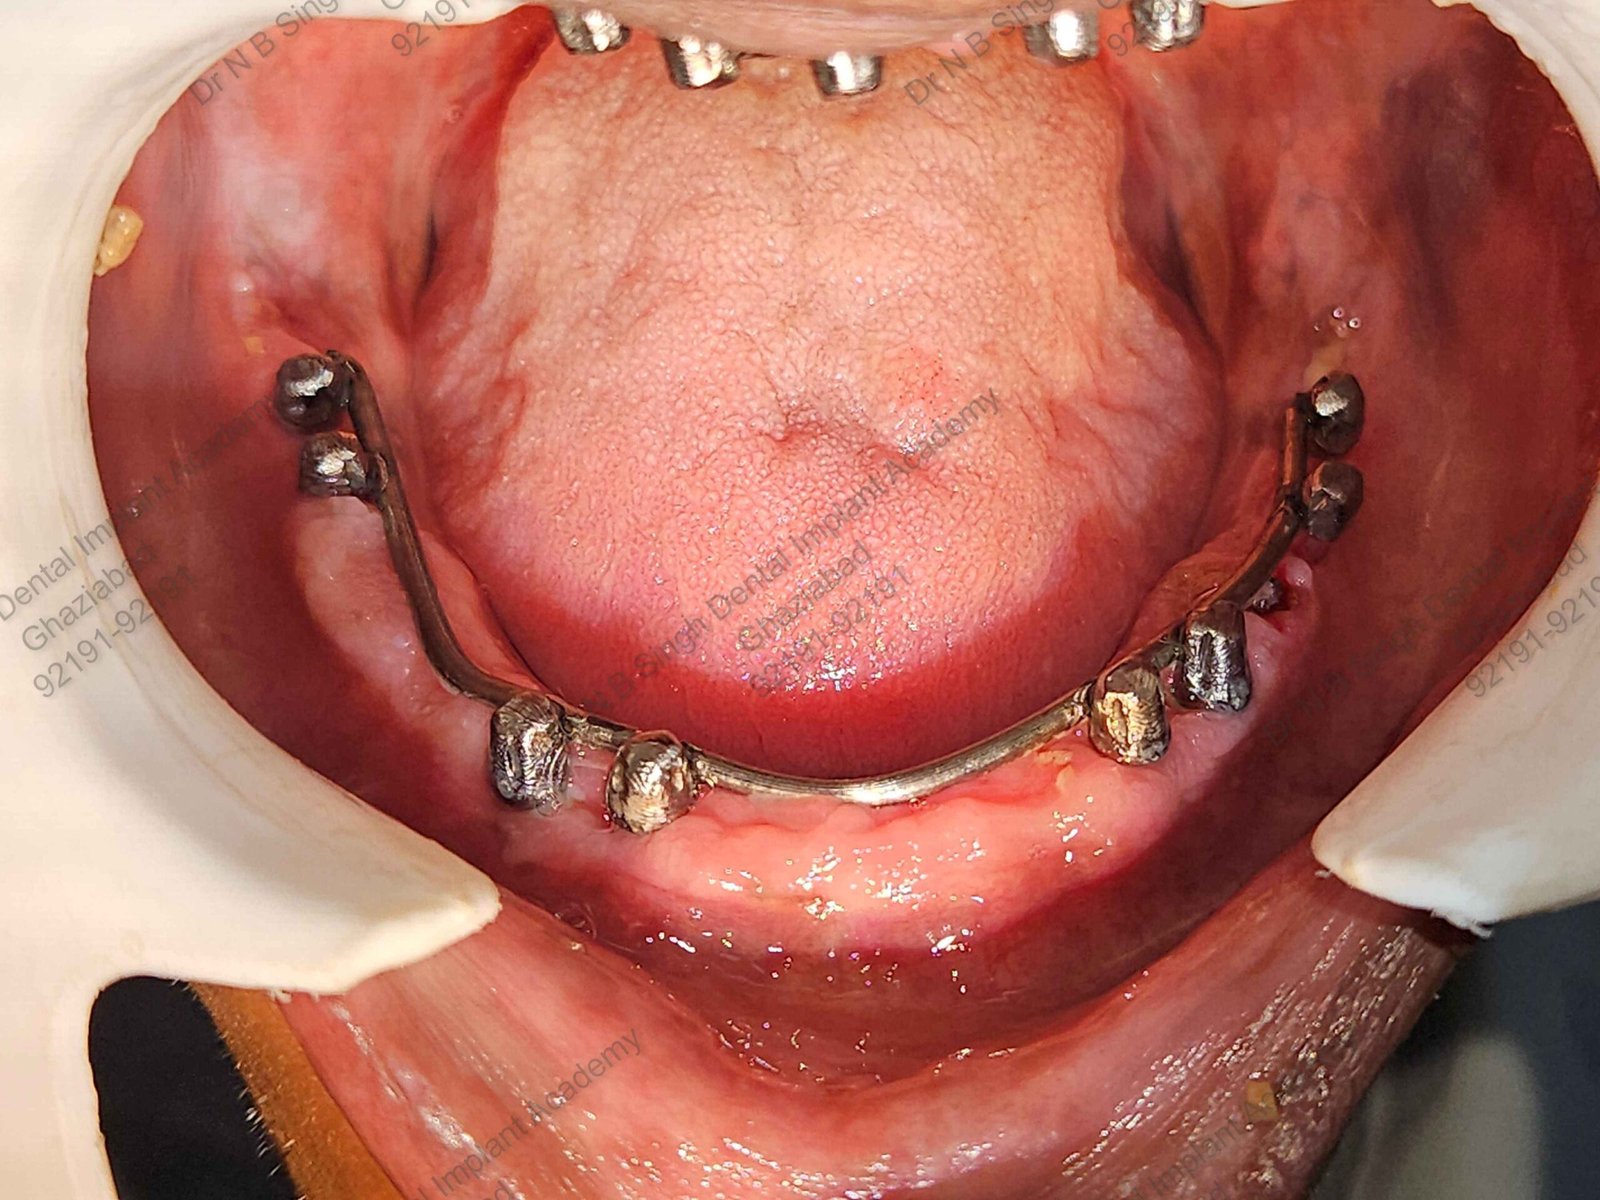

C1005 zygomatic basal implant full mouth – Ali Hasan 4